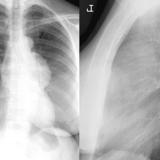

Case 1a

Thymoma